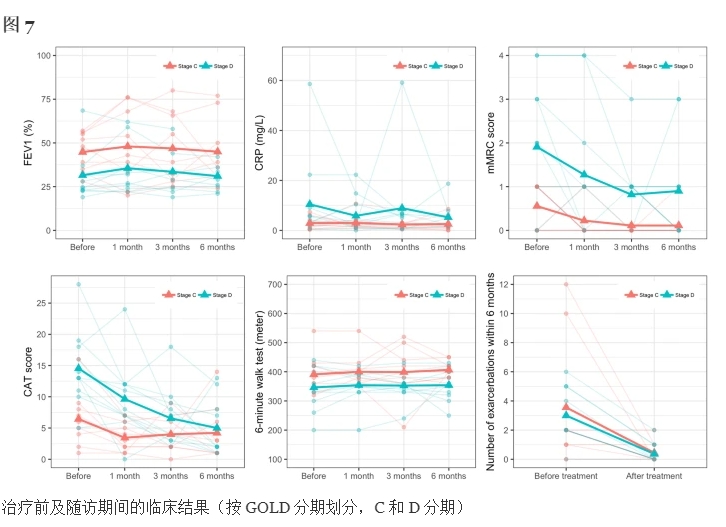

2.C期和D期患者的療效評(píng)估

- 圖7和表4顯示了結(jié)果,表明UC-MSC移植對(duì)D期COPD患者的治療效果優(yōu)于C期COPD患者。

- D期COPD患者治療3個(gè)月后mMRC、CAT值較治療前明顯改善,治療6個(gè)月后FEV1、CAT評(píng)分、發(fā)作次數(shù)較治療前明顯改善(P<0.05)。

- 6個(gè)月后兩組CRP值較治療前均下降約40%。